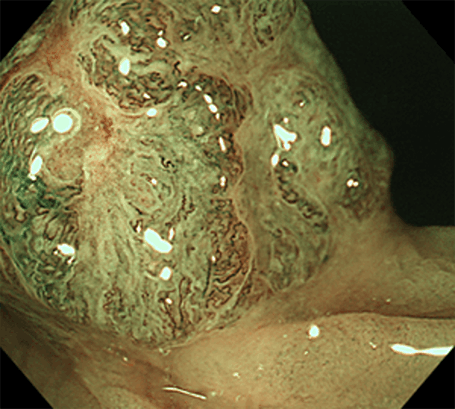

大腸過形成性ポリープ(右はNBI併用拡大観察像)

大腸腺腫(右はNBI併用拡大観察像)

SSL(右はNBI併用拡大観察像)